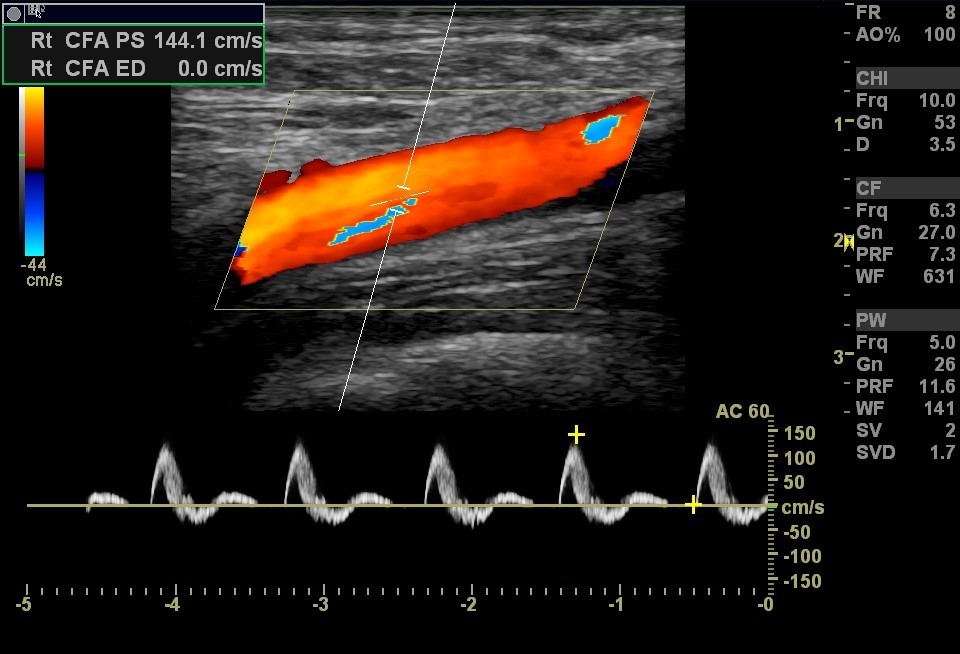

Lower Arterial Duplex Examination

When the sonographer assesses the arteries in the legs. Segmental pressures and pulse volume recording can also be included. The common iliac, external iliac, common femoral, superficial femoral, profunda, popliteal, anterior tibial, posterior tibial and peroneal arteries are typically assessed.

Lower Extremity Artery Ultrasound Image